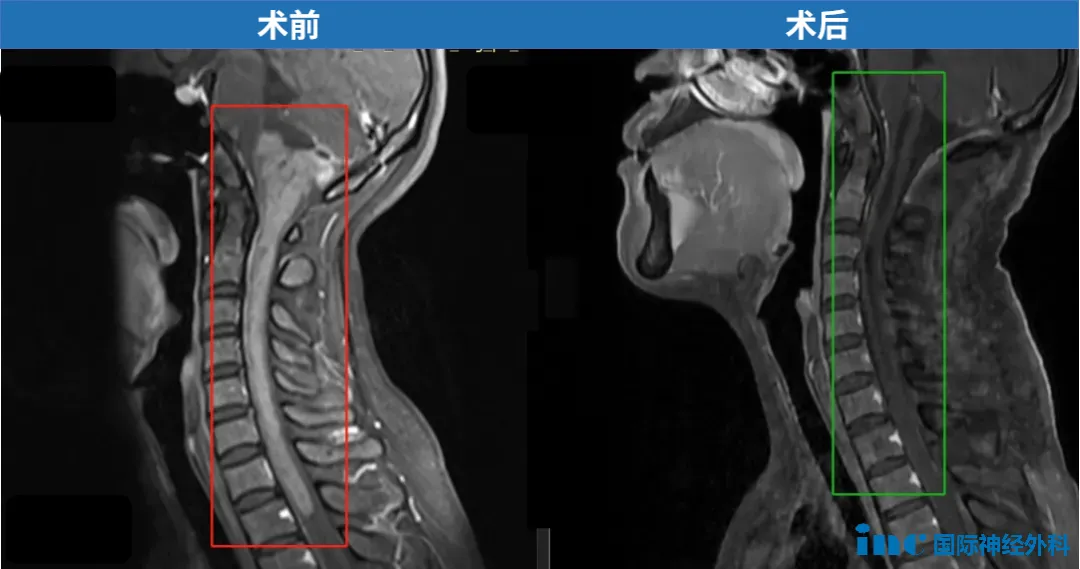

33岁,郑女士,15cm肿瘤起源于脑干下部,累及延髓和颅颈交界区,且向下方延伸到整个颈部脊髓以及一直到第一胸椎水平。2022年巴教授中国疑难示范手术,顺利近全切。

延髓胶质瘤手术案例

在同年出版的世界脑干手术专著《Brainstem Tumors》(脑干肿瘤)中,巴特朗菲教授撰写《Surgical Approaches to Medullary Tumors》(延髓肿瘤的外科手术方法)章节。这本具有启发性和综合性的著作,为读者提供了脑干手术的全面和详细的视角,以及有关病理诊断和治疗管理的先进的讨论。